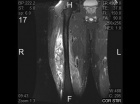

46 year old male noted some fullness in his right thigh about 5 months prior to presentation. Noticed some tense feelings in his thigh over the past month.

Zoom image: Radiological image Radiological image.